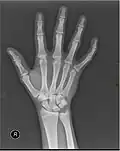

Fracture

The neck of a metacarpal is a common location for a boxer's fracture, but all parts of the metacarpal bone (including head, body and base) are susceptible to fracture. During their lifetime, 2.5% of individuals will experience at least one metacarpal fracture. Bennett's fracture (base of the thumb) is the most common.[4] Several types of treatment exist ranging from non-operative techniques, with or without immobilization, to operative techniques using closed or open reduction and internal fixation (ORIF). Generally, most fractures showing little or no displacement can be treated successfully without surgery.[5] Intraarticular fracture-dislocations of the metacarpal head or base may require surgical fixation, as fragment displacement affecting the joint surface is rarely tolerated well.[5]